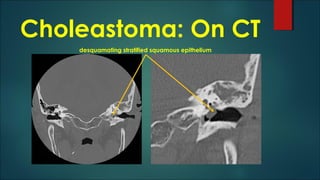

Choleastoma

 Epidermoid cyst composed of desquamating stratified squamous

epithelium

 Progressive accumulation of epithelial debris within their lumen

 Conductive hearing loss

 Congenital

 Epithelial rests within or adjacent to temporal bone

 Acquired

 Stratified squamous epithelium of the tympanic membrane

 retraction pockets

Choleastoma: On CT

desquamating stratified squamous epithelium

• #30 Cholesteatoma is histologically equivalent to an epidermoid cyst and is composed of desquamated keratinizing stratified squamous epithelium forming a mass. They usually present with conductive hearing loss. Congenital cholesteatomas originate from epithelial rests within or adjacent to the temporal bone. Acquired cholesteatomas originate from the stratified squamous epithelium of the tympanic membrane. These begin as localized tympanic membrane retraction pockets.

• #31 A CT scan should be added in those cases where a cholesteatoma is detected with MRI. CT is required for preoperative planning (reconstruction of ossicles if needed) and to exclude perforation of the bony tegmen. Pars flaccida cholesteatoma originates in Prussak&amp;apos;s space and usually extends posteriorly. Pars tensa cholesteatoma originates in posterior mesotympanum and tends to extend posteromedially.